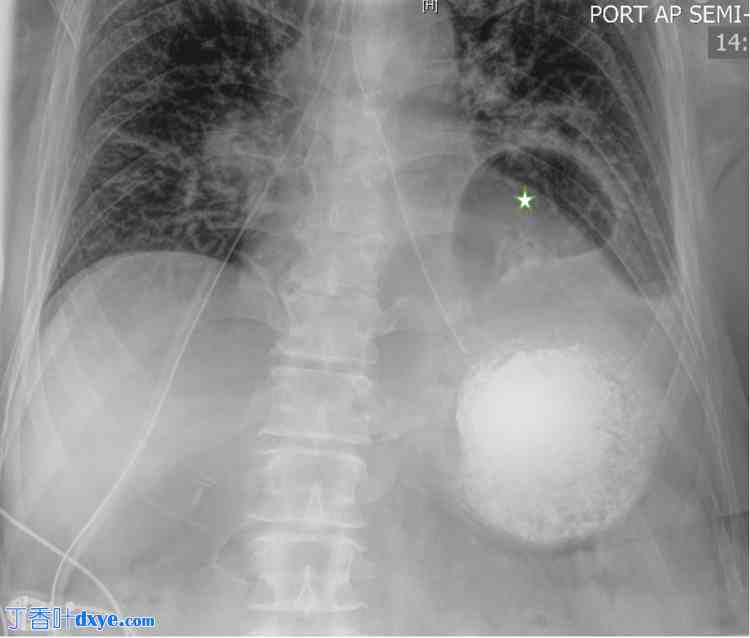

一名71岁男性,既往有脐疝修补术(使用网片)、高血压和胃食管反流病 (GERD) 病史,因胸腹痛伴呕吐到急诊就诊。症状于晚餐后出现,并逐渐加重,伴有腹胀和反复呕吐。未报告胃肠道出血的迹象。初始CT扫描显示,大量胃组织通过横膈膜突出至胸腔,无梗阻或穿孔征象(图1)。患者疑似胃肠炎和吞咽困难入院。

图1. 腹部CT扫描图像。

图像显示一个大的食管裂孔疝(标有星号)。